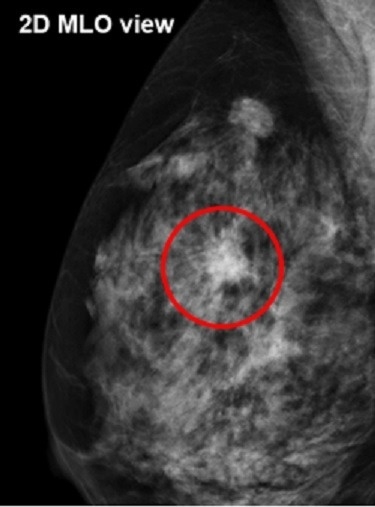

トモシンセシス(3Dマンモグラフィ)とは

通常のマンモグラフィでは、乳腺と病変部位が重なってしまい、判別しにくいことがあります。しかし、トモシンセシス撮影を用いることで、乳腺の重なりで見えにくかった病変を判別しやすくなり、検査精度の向上が期待できます。

検査例

通常のマンモグラフィ画像

赤丸の部分に腫瘤影

資料提供:GEヘルスケア